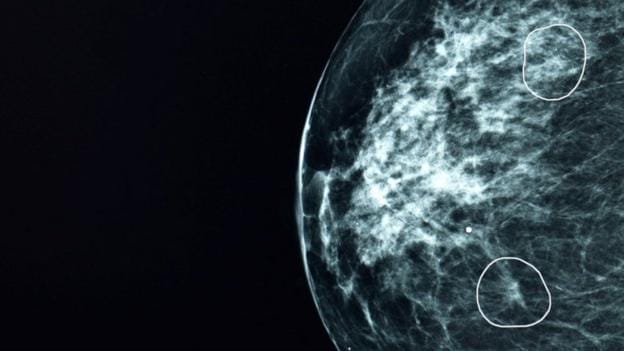

Mia, la herramienta de inteligencia artificial desarrollada por la compañía Kheiron Medical, ha demostrado su capacidad para identificar signos incipientes de cáncer de seno en mamografías que habían sido pasados por alto por los médicos. En un ensayo clínico realizado en varios centros de salud del Reino Unido, Mia analizó cerca de 10.000 mamografías, revelando la presencia de cáncer en 11 mujeres que no habían sido diagnosticadas previamente. Estos resultados son especialmente significativos dado que el cáncer de seno, en sus etapas iniciales, puede ser extremadamente difícil de detectar y los tumores pueden ser prácticamente invisibles al ojo humano.